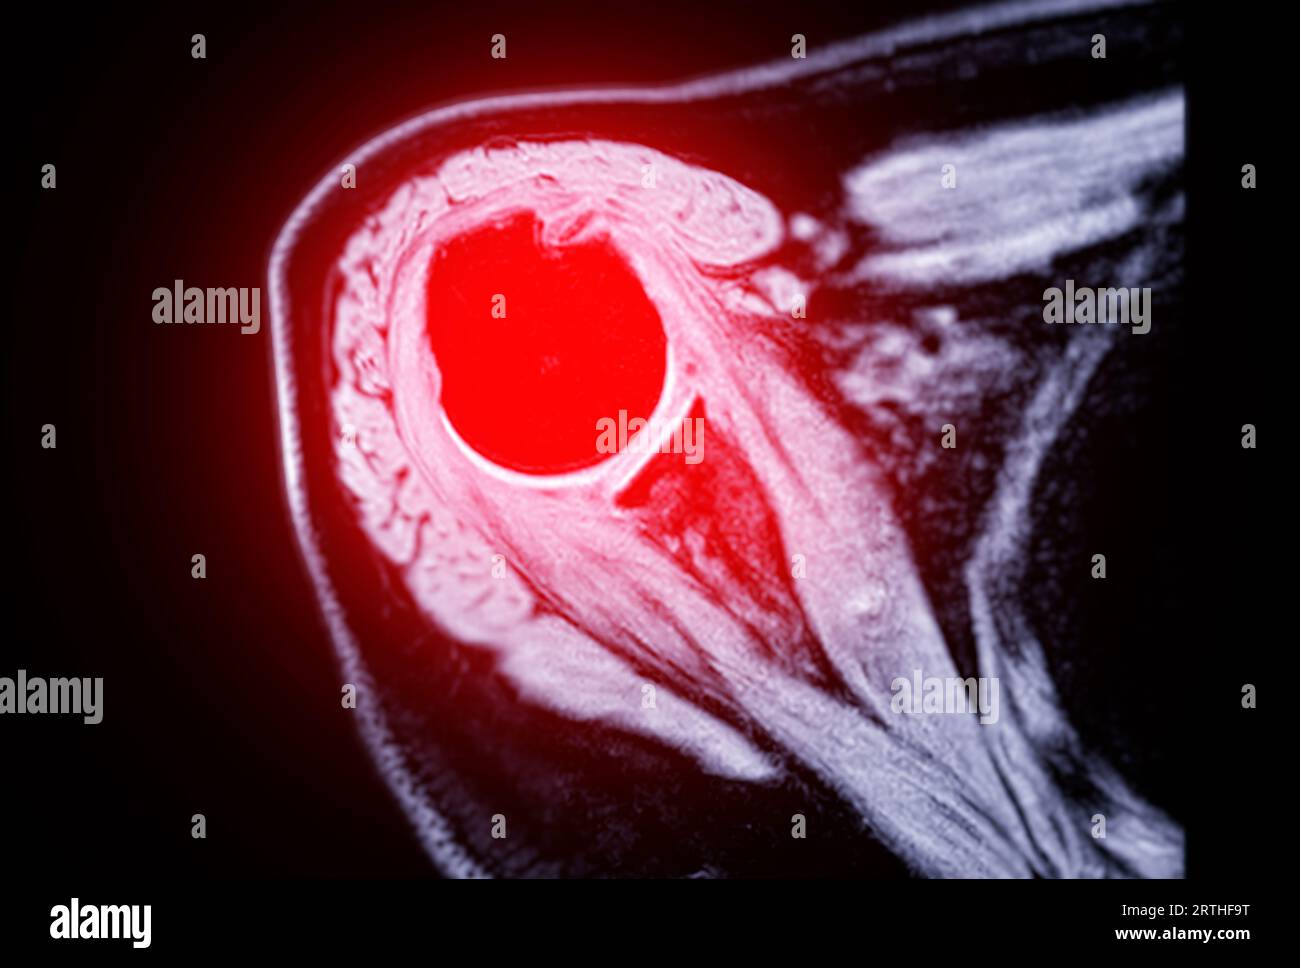

Resonance Imaging or MRI of Shoulder Joint Coronal T2 FS and PDW for diagnostic What Can Mri Of Shoulder Detect magnetic resonance imaging (mri) of the shoulder is done to: magnetic resonance imaging (mri) of the shoulder uses a powerful magnetic field, radio waves and a computer to produce. The mri allows accurate assessment of. a shoulder mri is a test that uses a magnetic field to take pictures of your shoulder. A shoulder mri can diagnose. What Can Mri Of Shoulder Detect.

Resonance Imaging or MRI of Shoulder Joint for diagnostic shoulder pain Stock Photo Alamy What Can Mri Of Shoulder Detect A shoulder mri can diagnose tears of the rotator cuff, labrum, and tendons. a shoulder mri is a test that uses a magnetic field to take pictures of your shoulder. magnetic resonance imaging, or mri, uses a magnet to examine the inside of your body, useful for diagnosing shoulder pain and. the evaluation of the shoulder, and. What Can Mri Of Shoulder Detect.